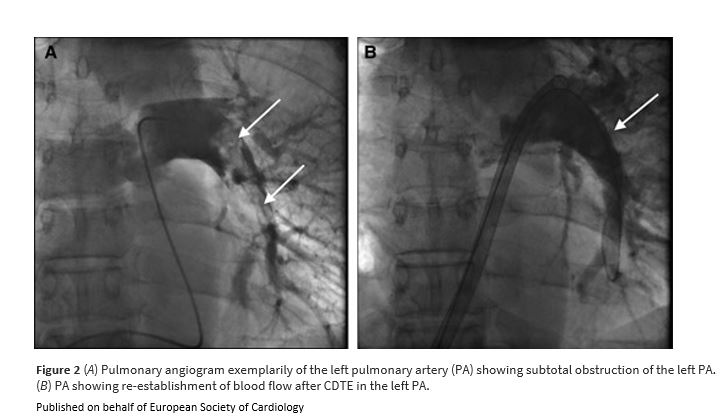

Unexpected paradoxical embolisation following catheter-directed thrombectomy with the FlowTriever™ system in a case of pulmonary embolism bit.ly/41n1RlZ

#EHJCaseReports #EchoFirst @aayshacader @KardiologieHH @ANazmiCalik @EHJCREiC @TJ_Yeo @Phiso_de @FarhanaAra